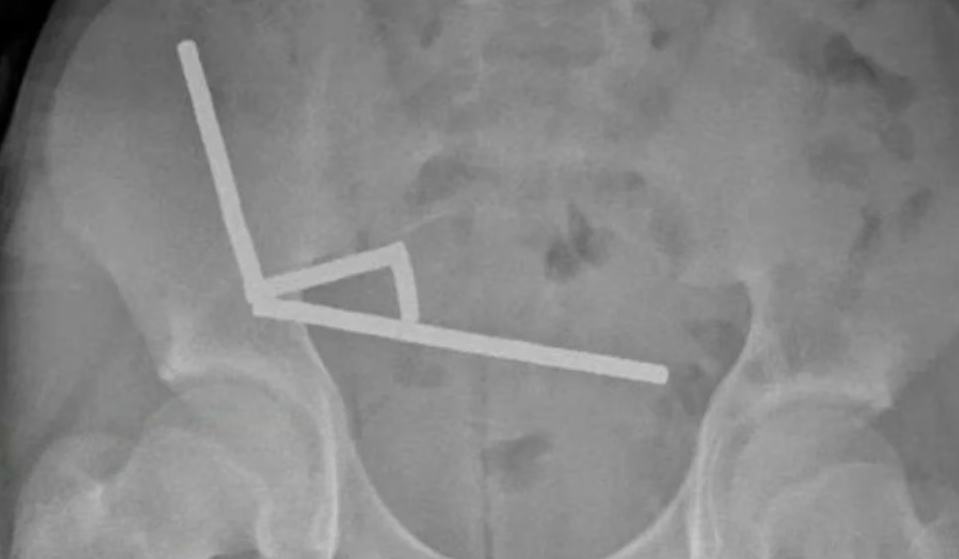

Magneti su se u njegovom tijelu čvrsto vezali jedan za drugi. Doktori su koristili rendgenske zrake kako bi otkrili četiri lanca magneta, raspoređena po različitim dijelovima njegovih crijeva. Tokom operacije, otkrili su da se ovi lanci nalaze u njegovom tankom crijevu i slijepom crijevu. Budući da su se magneti tako čvrsto vezali, uzrokovali su nedostatak protoka krvi i odumiranje dijela crijevnog tkiva zbog pritiska.